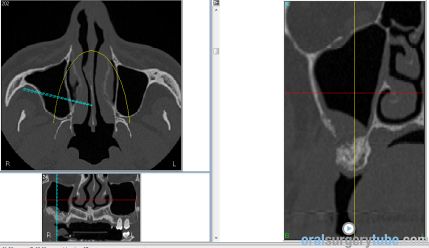

Con este comentario haremos una pausa en el caso hasta que llegue la colocación de los implantes. Por el momento, está todo solucionado. No hay sintomatología alguna, y lo más importante, en TAC realizado el martes 31.07.2018, podemos ver que el seno ha drenado por completo y está aireado. Hasta nuevo aviso, suspendemos todo tipo de medicación. Subimos imágenes del último TAC donde podemos apreciar que hemos perdido algo de xenoinjerto, pero la zona de menor altura aún tiene 10 mm. Podemos ver en una de las imágenes la zona de la ventana por donde el seno drenaba. Esperaremos el tiempo reglamentario para poder reevaluar si el xenoinjerto sigue siendo viable. Ha sido un gran placer contar con este equipo y poder aportar un grano de arena a solucionar complicaciones quirúrgicas.

Continúo con el seguimiento que vamos dando a este paciente: Visitado el miércoles 11.07.2018. Hay ausencia total de sintmatología. Retiramos el drenaje, hacemos Prueba de Valsalva positiva, pero sale aire y un poco de sangre. Dejamos cicatrizar por segunda intención. Pedimos continuar la medicación antibiótica y solicitamos un TAC. El seno maxilar está ocupado como vemos en la imagen, pero el biomaterial está contenido en la zona injertada: no existe ningún gránulo de xenoinjerto dentro del seno. La apófisis mastoidea está aireada.